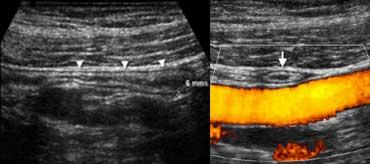

Ruột thừa bình thường: Siêu âm mặt cắt dọc (A) cho thấy một cấu trúc hình ống tận cùng mù (đầu mũi tên) với ‘dấu hiệu ruột’, đường kính ngoài tối đa 6 mm, xung quanh là lớp mỡ không viêm. Trên mặt cắt ngang (B), ruột thừa có thể bị ép xẹp khi đi ngang qua các mạch máu chậu.

Ruột thừa bình thường.

Ruột thừa bình thường: CT cho thấy ruột thừa chứa khí, không giãn (đầu mũi tên), với lớp mỡ quanh ruột thừa đồng nhất, giảm tỷ trọng.

Ruột thừa bình thường có đường kính tối đa 6 mm, được bao quanh bởi lớp mỡ đồng nhất không viêm, có thể ép xẹp và thường chứa khí trong lòng.

Ruột thừa viêm trên siêu âm. Mặt cắt dọc (A) và mặt cắt ngang (B) cho thấy ruột thừa giãn, không ép xẹp được, được bao quanh bởi lớp mỡ viêm tăng âm (đầu mũi tên).

Ruột thừa viêm

Ruột thừa viêm có đường kính lớn hơn 6 mm và thường được bao quanh bởi lớp mỡ viêm. Sự hiện diện của sỏi phân (fecolith) hoặc tăng sinh mạch máu trên Doppler năng lượng là những dấu hiệu hỗ trợ mạnh mẽ cho chẩn đoán viêm.